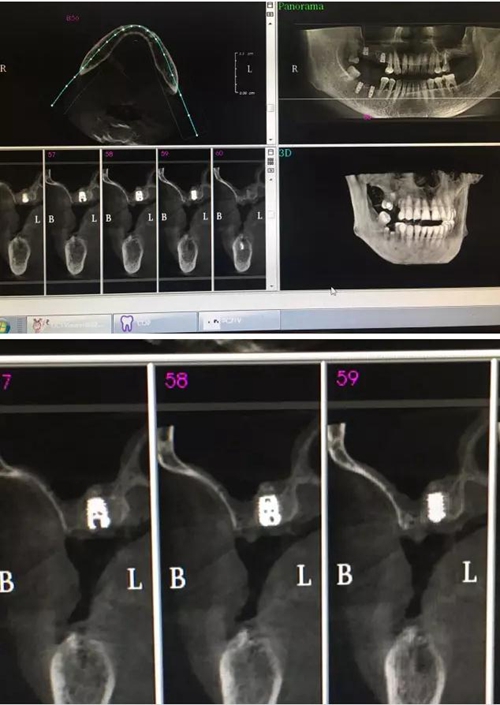

【病例分享】內(nèi)提,用自體骨柱,不用骨粉

4.jpg